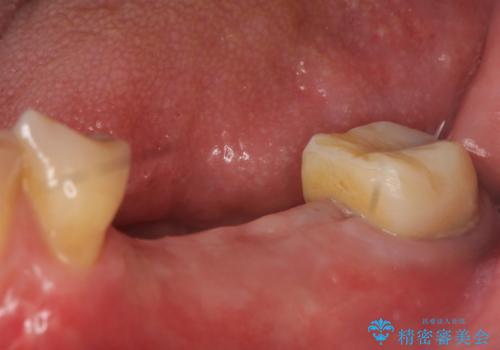

- 左下奥歯が虫歯で抜歯になってしまったため、インプラントにしたいといらっしゃった方の症例です。

欠損部位である左下5、6番目にインプラントを埋入し、オールセラミッククラウンによる補綴を行いました。